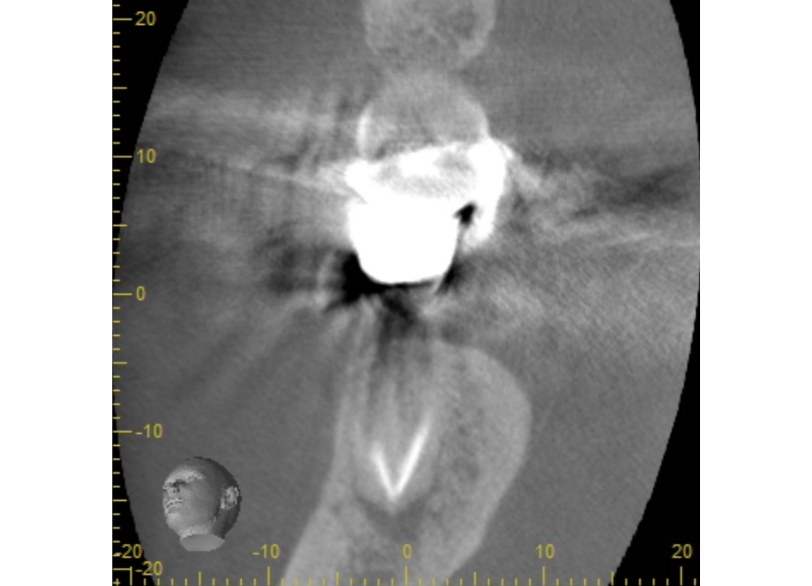

②術前CTによる根尖部の未治療および根尖透過像

| 診断 | 右下6.7根尖性歯周炎 | ||||

| 処置内容 (または主訴) | マイクロスコープ治療を用いた感染根管治療 | ||||